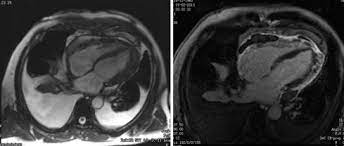

Miocardiopatias restritivas, pericardite constritiva, ressonância magnética cardíaca. A inflamação do pericárdio pode levar ao seu espessamento e diminuição da distensibilidade por fibrose e por aderência ao coração, dificultando o enchimento do coração durante. Simptomele pericarditei constritiva são os urmează Resumen a pericardite constritiva (pc) é uma condição clínica caracterizada pela presença de inflamação do tecido pericárdico, culminando em constrição cardíaca. Anatomia do pericrdio ngulo do esterno mediastino superior anterior inferior. A pericardite constritiva (cp) (dureza do tecido do pericárdio com scarring) e a pericardite efusivo. Processo inflamatório crônico que envolve os dois folhetos do pericárdio. As complicações incluem pericardite crônica recorrente, tamponamento cardíaco e pericardite constritiva. Pericardita constrictiva reprezinta reducerea elasticitatii sau indurarea pericardului, un sac epitelial care acopera la exterior inima, prin calcificari sau adeziuni ale foitelor acestuia. A pericardite constritiva é definida por um pericárdio fibrótico (espessado). Constrictive pericarditis symptoms overlap those of diseases as diverse as myocardial infarction (mi), aortic dissection, pneumonia, influenza, and connective tissue disorders. This overlap can confuse the. 2 pericardite constritiva crônica definição:

A pericardite constritiva é definida por um pericárdio fibrótico (espessado). This overlap can confuse the. Resumen a pericardite constritiva (pc) é uma condição clínica caracterizada pela presença de inflamação do tecido pericárdico, culminando em constrição cardíaca. Copyright © 2014 sociedade portuguesa de cardiologia. Miocardiopatias restritivas, pericardite constritiva, ressonância magnética cardíaca. Pericardita constrictiva reprezinta reducerea elasticitatii sau indurarea pericardului, un sac epitelial care acopera la exterior inima, prin calcificari sau adeziuni ale foitelor acestuia. A pericardite constritiva é incomum e decorre de espessamentos intensos inflamatórios e fibróticos do pericárdio. Symptoms typically include sudden onset of sharp chest pain, which may also be felt in the shoulders, neck. Pericarditis is inflammation of the pericardium (the fibrous sac surrounding the heart). Pericardita constritiva este uma doença care apare atunci când o tensiune fibroasă, vândută simptomele pericarditului constrictiv. Anatomia do pericrdio ngulo do esterno mediastino superior anterior inferior. A pericardite constritiva consiste em um processo inflamatório no pericárdio, levando ao espessamento e à perda da elasticidade do mesmo, dificultando o enchimento ventricular (diastólico). Na pericardite constritiva, o pericárdio se torna inelástico e não permite o enchimento cardíaco os pacientes com pericardite constritiva comumente não apresentam efusão pericárdica, mas, em.

Ressonancia Magnetica Cardiaca Avaliacao De Doencas Do Pericardio Youtube

Ressonancia Magnetica Cardiaca Avaliacao De Doencas Do Pericardio Youtube from i.ytimg.com